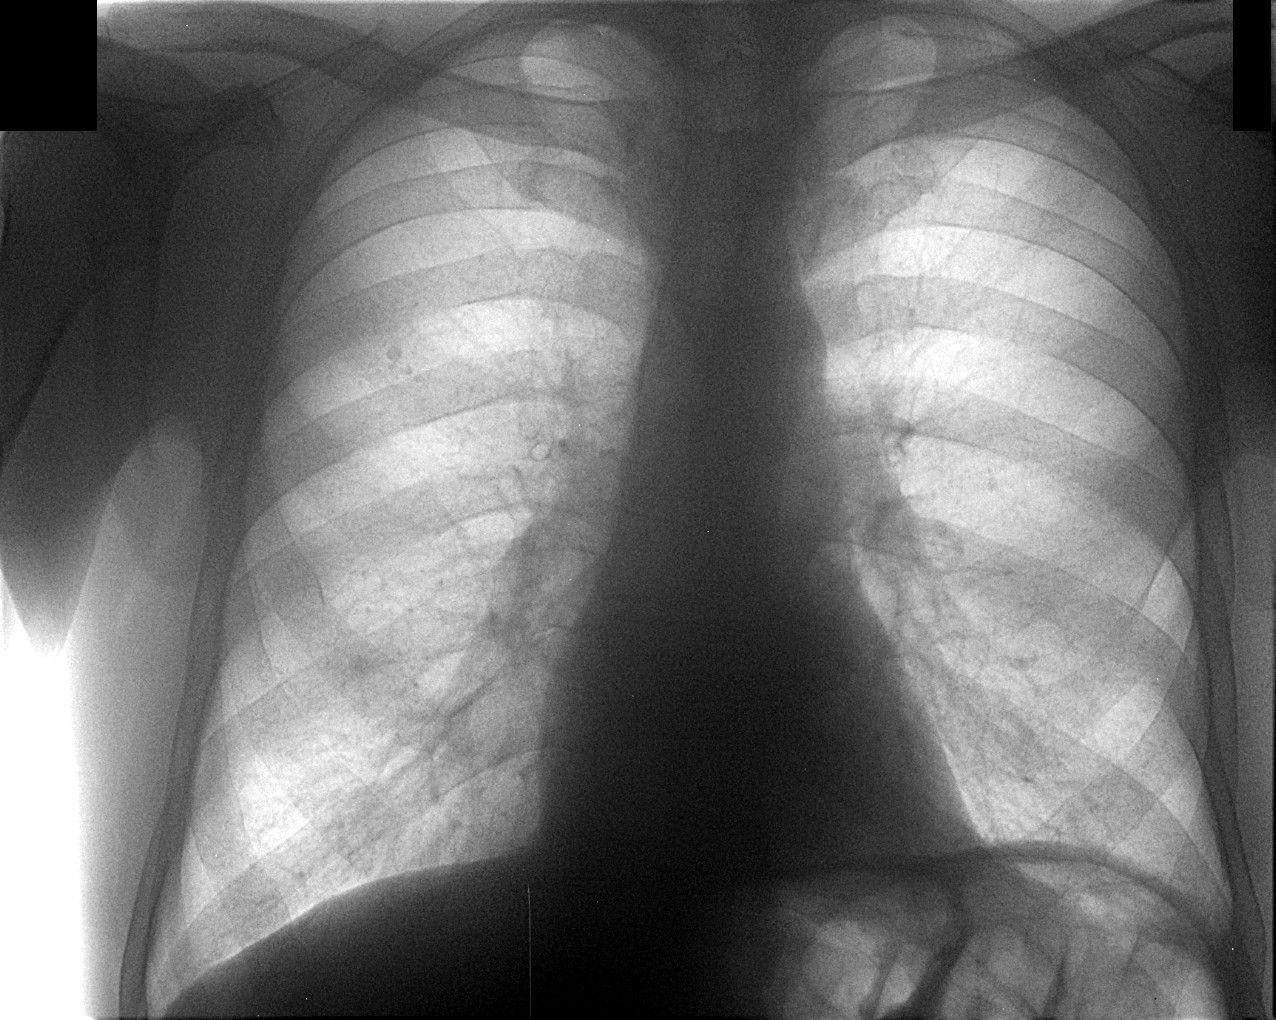

Priamoi.jpg

Через 10 дней направлен повторно, диагноз - пневмония слева. Прямой снимок без признаков инфильтрации, учитывая клинику (интоксикация, гектическая температура, боль в лев. половине гр. кл.), решили посмотреть за сердцем в лев. косом положении, лев. боковой сам Бог велел (снимки представлены). Посмотрели и скопически: в S10 инфильтрация с участками просветления, в заключении написали - пневмония, но термин "абсцедирование" решили не применять, хотя "в уме держали". Больного направили в т/о, там почему-то усомнились в нашей диагностике, пациент вернулся: "меня направляют на Р-гр". Пришлось связаться с терапевтами и прочитать лекцию о том, кто и за что отвечает. На следующий день терапевты с завидным упрямством настаивают на контрольной Р-гр., говорят - боимся абсцедирования, хорошо - говорю, договариваюсь с кэтэшниками, "прокатили" грудную клетку. Но ничего нового, дополнительного не нашли, а "просветлениями" оказались просветы бронхов. Инфильтрация расположена пристеночно, прилежит к позвоночнику с переходом на заднюю стенку гр. клетки, именно в связи с этим никак не прявляет себя на прямом снимке и на боковом выглядит не слишком убедительно. Наиболее оптимальными для такого расположения являются передняя левая или задняя правая косые проекции. Еще через 10 дней, при контрольной рентгеноргафии (прямая и левая боковая), картина без признаков инфильтрации, зная особенности случая, беру за экран и при указанных выше положениях вижу остатки инфильтрации, трактую как "остаточные изменения после пневмонии". Клинически - пациент бъет себя в грудь: "все прекрасно, домой хочу!".

Иконка изображения Priamoi.jpg150.08 КБ